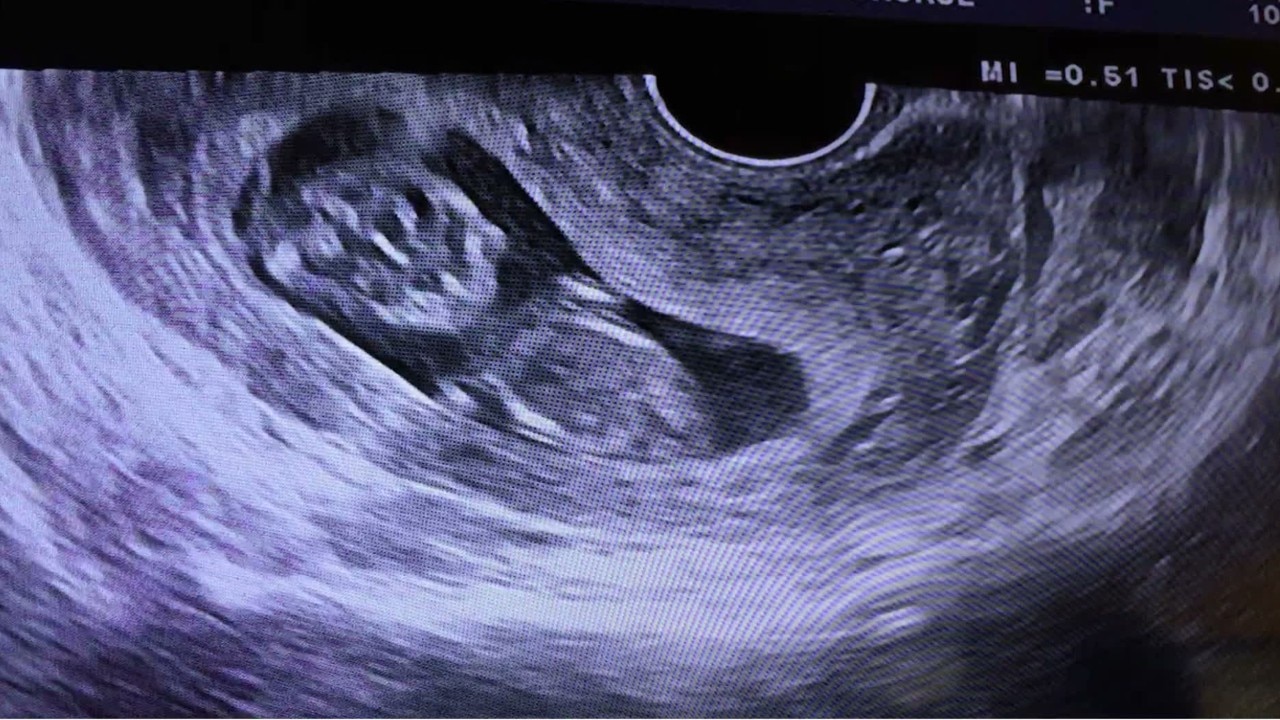

Louisiana lawmakers on Wednesday passed a strict new abortion ban that would prohibit the procedure before some women even know they are pregnant, joining a half-dozen conservative states with similar measures.